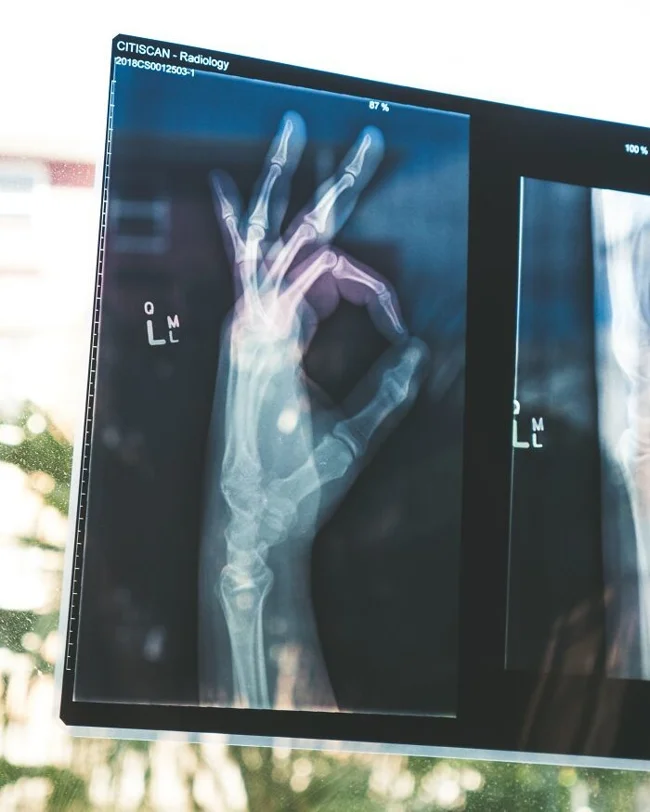

"Когда рентгенография только стала широко доступна для педиатров, они стали замечать огромное количество переломов. Озадаченные врачи предположили, что обнаружили ранее неизвестное заболевание костей у детей. Оказалось, что люди просто не подозревали, насколько распространено жестокое обращение с детьми".